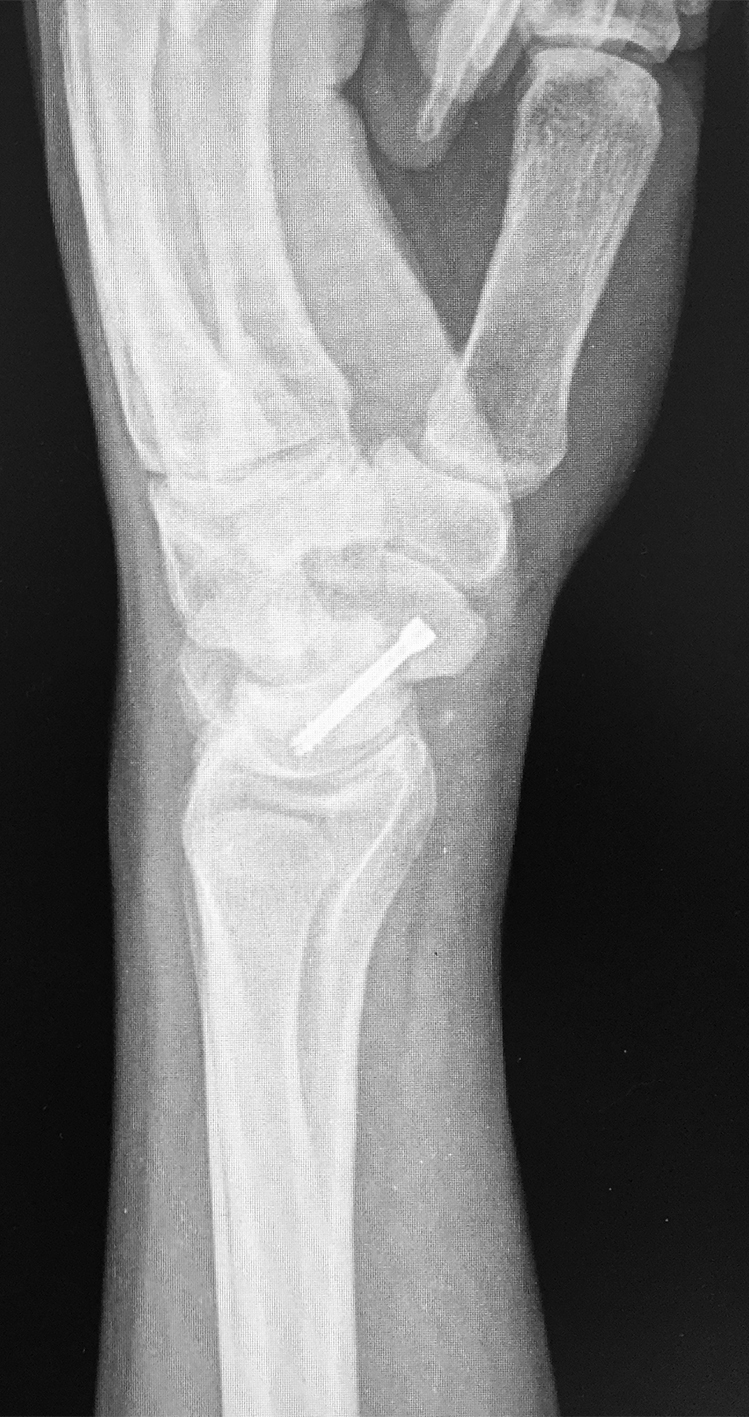

Efectuamos un abordaje volar dado que conserva la vascularización dorsal, permitía la visualización directa del foco, movilización de los polos y manejar la deformidad en joroba mediante el injerto trapezoidal (1)(11)(12). Nos centramos sobre el tendón palmar mayor, efectuando una incisión curvilínea dirigida hacia el tubérculo del escafoides. Se protegió la rama sensitiva cutánea del nervio radial y disecamos el plano superficial incidiendo la cápsula longitudinalmente sobre el eje del escafoides. Se reflejó la cápsula, se identificó el polo distal y proximal colocando dos agujas de Kirschner, a modo de joystick. Cureteamos el foco con una fresa (Figura 1). Dejando el escafoides, extrajimos un injerto cortico-esponjoso trapezoidal de cresta iliaca (Figura 2). Volviendo a la mano, distrajimos los fragmentos escafoideos y colocamos el injerto, con su base en situación volar, para extender el escafoides (1)(5)(12)(13). Colocamos otra aguja de Kirschner retrógrado como guía, y tras medir y mechar, colocamos un tornillo de compresión interfragmentaria (11), para proceder posteriormente a cerrar la cápsula y los planos superficiales. Se colocó una inmovilización con férula de yeso, incluyendo el primer dedo, que mantuvimos durante 4 semanas.

Se efectuaron radiografías dorso-palmar, lateral pre y post operatorias. Al final del seguimiento se evaluó la consolidación mediante radiografías. Se indicó un TC de puño en los pacientes como método de valoración pre operatoria y la RM cuando se sospechó un compromiso vascular del polo proximal para definir técnica quirúrgica.

La evaluación de la movilidad mostró que 5 pacientes (29,4%) tenían la movilidad completa; 11 pacientes (64,7%) la conservaron entre el 75 y el 99 % y un paciente (5,9%) entre el 50 y el 74%. No encontramos asociación estadística entre la movilidad y el retraso terapéutico (p=0,241). (Figura 3) (Figura 4) (Figura 5) (Tabla 1) (Tabla 2).

Figura 3: Caso 9

a) Radiografia de perfil pre-opertaoria

b) TC pre-operatoria. Corte sagital

c) TC pre-operatoria. Corte coronal

d) Radiografías post-operatorias

e) Radiografía de frente, 33 meses seguimiento, pseuodartrosis persistente

f) Radiografía de frente, 33 meses seguimiento, pseuodartrosis persistente